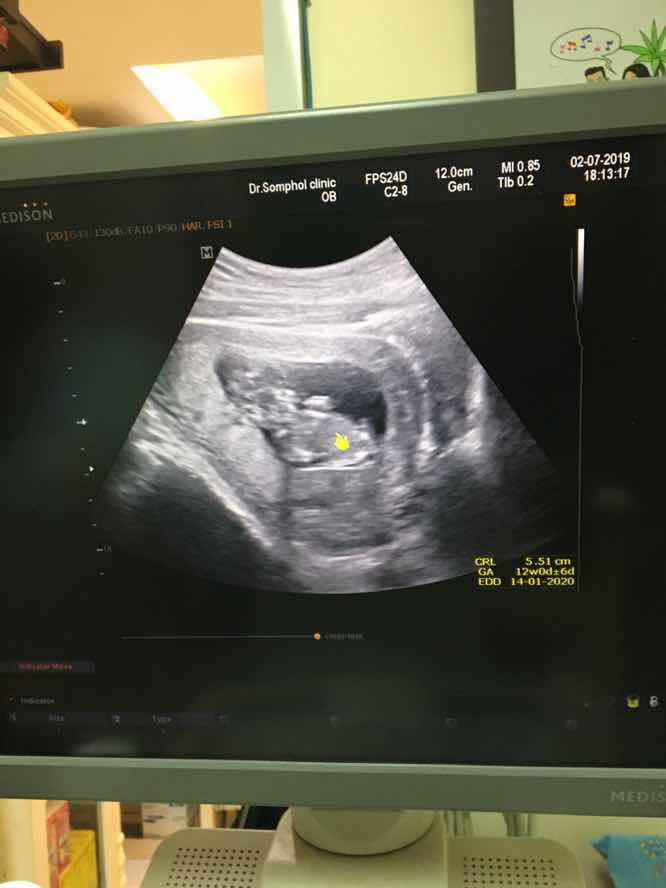

12 week ka

12 วีค4วันจ้า

12วีคค่ะ💕

ตอน12wค่ะ

12วีคค่ะ

12w2d จ้า